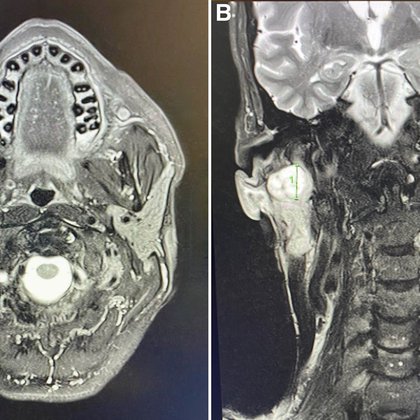

As if you needed further proof that @nigeltwitt is awesome, he even publishes his own clinical case in the @PIDJournal 🤣🥰 A Pain in the Neck Sixty Years On : The Pediatric Infectious Disease Journal

This report describes the recurrence of an infected first branchial cleft cyst in an adult and highlights the importance of considering branchial cleft cysts in the differential diagnosis of cervical...